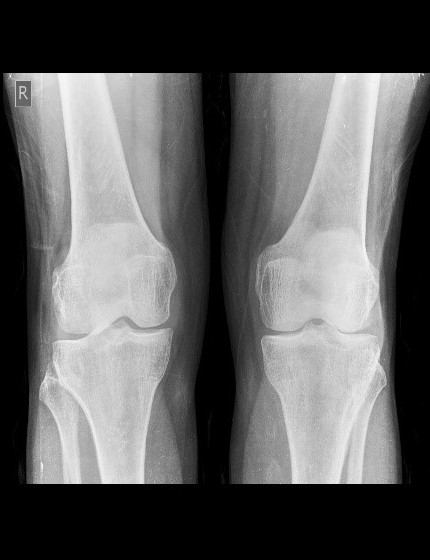

The dataset used in this research was collected by the Unani and Panchakarma Hospital, Srinagar, J&K, India [17]. It included X-ray images of the knee along with patient clinical data, covering variables such as gender, height (in meters), age, history of fractures, medical history, dialysis, joint pain, alcohol consumption, and site, which displayed identical values across different classes. Additional features, such as obesity, smoking habits, daily eating habits, diabetes, seizure disorders, family history of osteoporosis, and hypothyroidism, were also collected. However, these features were excluded as they were found to be uninformative based on feature importance analysis. Furthermore, variables with sparse data, such as the number of pregnancies and menopause age, were removed due to their limited availability across patients. Statistical details of the remaining key features, which were found to be most informative, are presented in Fig. 1. This study addresses a three-class classification problem, with the target categories being normal, osteopenia, and osteoporosis (2). Normal bone density reflects healthy bones with typical mineral levels. Osteopenia describes a condition where bone mineral density (BMD) is lower than normal but not yet low enough to be classified as osteoporosis. Osteoporosis represents a more severe reduction in BMD, resulting in brittle bones that are highly susceptible to fractures. Representative examples of X-ray images for each class are presented in Fig. 3. To streamline processing and ensure the model focused on the most relevant areas, regions of interest (ROI) were identified in the X-ray images. For patients with images of both knees, we randomly selected the left or right knee for analysis. The preprocessed X-ray images were then fed into pre-trained models for feature extraction.